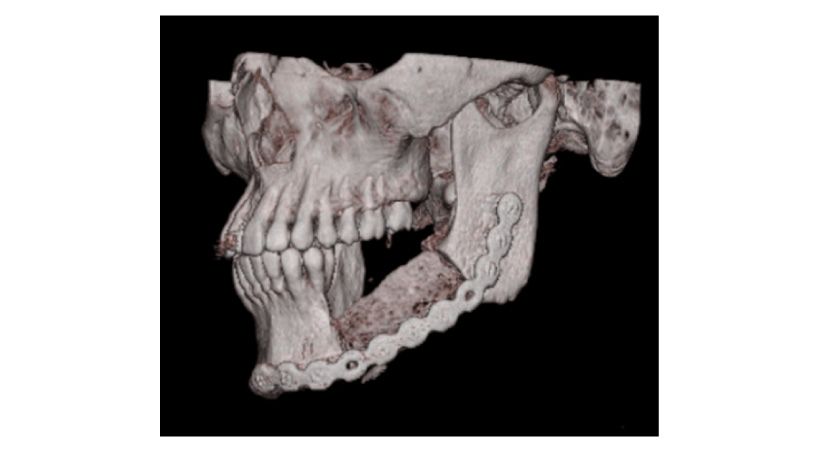

Condiciones de aplicación del injerto ilíaco óseo en la sustitución de defectos mandibulares

Un estudio retrospectivo de 11 años de experiencia